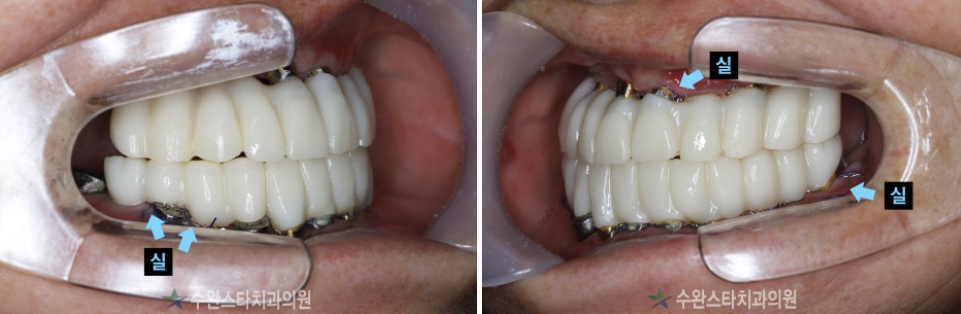

임시치아 (수술 후 3일 경과)

임시치아 구강 내부, 60대 여성 (2024.12 촬영)

환자분의 원활한 식사를 위해

실도 빼기 전인

수술 후 3일 만에

치아 넣어드렸습니다.